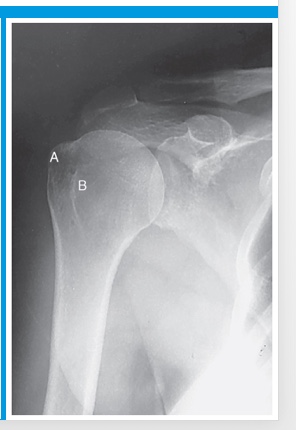

clavicle

A

coracoid process

B

glenoid fossa

C

acromion process

D

lesser tubercle

E

humeral head

F

external rotation

position of humerus?